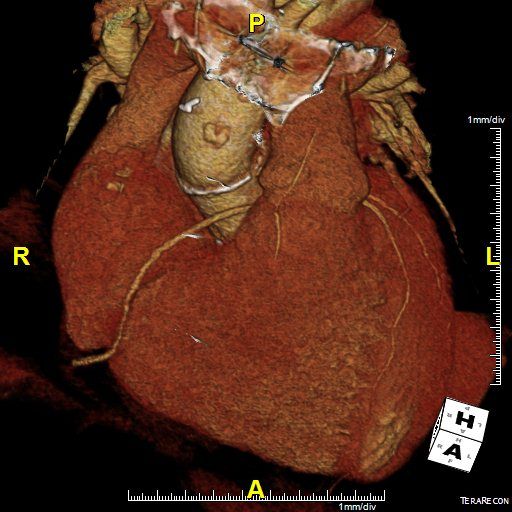

Routine CT angiography for patients with diabetes not more effective in preventing cardiovascular complications than good standard of care.

Coronary CT angiography may become an important part NAFLD assessment.